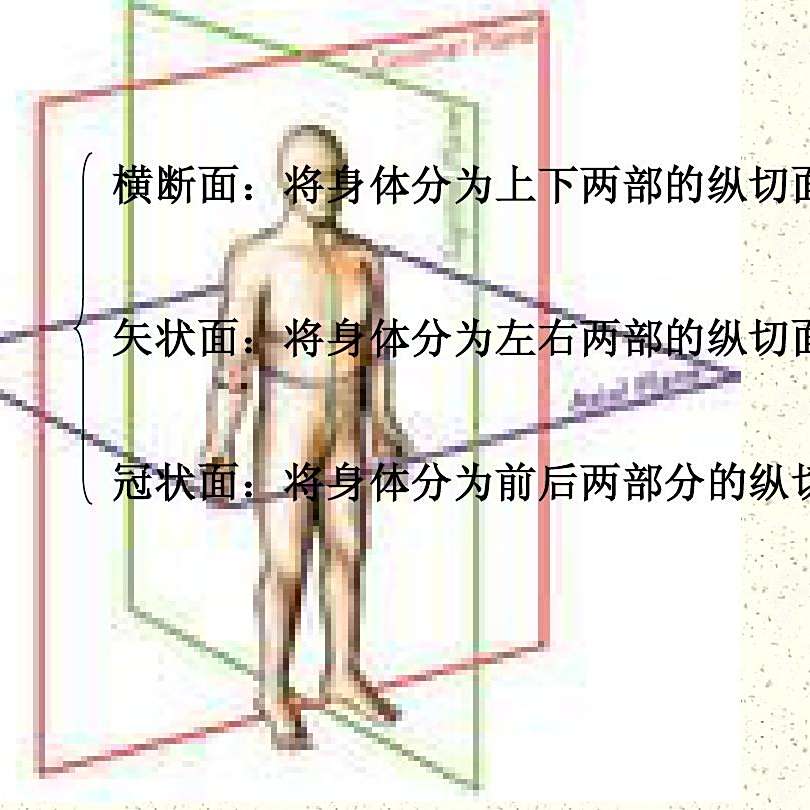

矢状面、冠状面、水平面が分からない? これで完全理解!! 身体の方向をあらわす3つの基準面 矢状面、冠状面、水平面 、本当に理解している?ここって、結構間違えやすい部分だよね。 なので、今回は「矢状面 正中面 」「冠状面」「水平面」のそれぞれの覚え方を。

矢状面、冠状面、水平面が分からない? これで完全理解!! 身体の方向をあらわす3つの基準面 矢状面、冠状面、水平面 、本当に理解している?ここって、結構間違えやすい部分だよね。 なので、今回は「矢状面 正中面 」「冠状面」「水平面」のそれぞれの覚え方を。

矢状面、冠状面、水平面が分からない? これで完全理解!! 身体の方向をあらわす3つの基準面 矢状面、冠状面、水平面 、本当に理解している?ここって、結構間違えやすい部分だよね。 なので、今回は「矢状面 正中面 」「冠状面」「水平面」のそれぞれの覚え方を。

矢状面、冠状面、水平面が分からない? これで完全理解!! 身体の方向をあらわす3つの基準面 矢状面、冠状面、水平面 、本当に理解している?ここって、結構間違えやすい部分だよね。 なので、今回は「矢状面 正中面 」「冠状面」「水平面」のそれぞれの覚え方を。

horizontal sagittal and coronal planes水平面,矢状面,冠状面 _sigittal coronalhorizontal之间的区别-CSDN博客。

强强的个人技术博客-医学中水平位、冠状位、矢状位这三个位置的概念分别是什么。

分清frontal plane 额状面 、coronal plane 冠状面 、transverse plane 横断面 、sagittalplane 矢状面 -CSDN博客。

关于医学影像中的轴位面 横断面 、冠状面、矢状面的解释_ct轴位和冠状位的区别-CSDN博客。

关于医学影像中的轴位面 横断面 、冠状面、矢状面_轴状位-CSDN博客。

医学图像的三个主要平面:矢状面、冠状面、横断面_冠状面和矢状面示意图-CSDN博客。